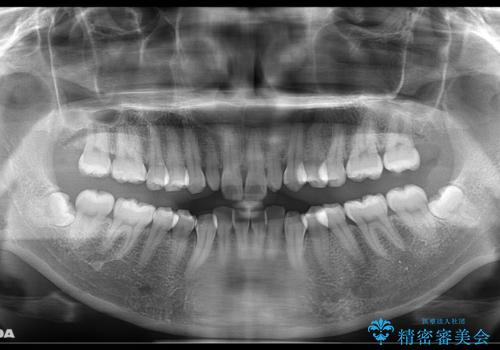

- 上の前歯が大きい事と下の前歯のがたつきを気にされてご相談にいらした方です。上の2番目の歯が矮小歯であったため、矯正治療にて歯のスペースを作った後、矮小歯には被せ物をして前歯のバランスを整えました。